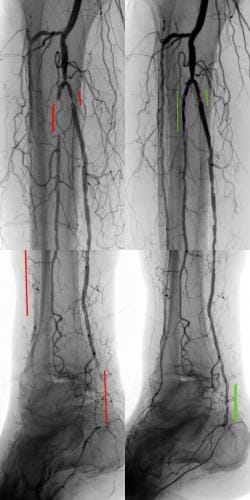

- What is the experience? Choose a specialist that has a proven record of tackling difficult cases successfully. Some specialist choose to only do the simple procedures and refer the rest to surgery. Additionally, if the specialist can only perform simple procedures they may have a higher rate of complication if the case turns out to be more difficult than expected. Our specialist has performed numerous successful complex procedures from the groin, knee and foot. See our prior cases here.

During these procedures: Sedation is given to help you relax. Next, a tiny tube is gently inserted in an artery, usually in the groin or upper thigh area. You will be given a local anesthetic to numb the area where the tube will be inserted. It is then guided through the blood vessel toward the disease artery. When it’s in place, a dye is injected through the catheter to visualize the arteries. An X-ray is taken to help the physician pinpoint the area that is blocked or narrowed. The physician then uses tiny wires and catheters to get through the diseased vessels. Depending on the images treatment may then be performed.

Our Vascular and Interventional Radiologist will devise an individualized treatment plan designed to minimize pain, cure sores, avoid amputation, and improve the overall quality of life for our patients. It is our goal to stay on top of all disease progression to keep you on your feet. Patient care does not end after a procedure. Follow-up appointments are scheduled to evaluate recovery and results, and personable staff members and physicians will be available to help with questions or concerns after every procedure, diagnostic test, and appointment. We are dedicated to giving each patient the best possible experience and results.

Superior catheter and wire skills is essential in a delicate procedure such as treating blocked arteries. We treat a number of patients that have had failures by other specialists. Our doctor is an image-guided specialist having performed over 5,000 procedures with successful experience in venous and arterial blockages. Having a wide array of experience in different image-guided procedures brings a unique skill set to ensure that you have the most successful outcome without complication. Rest assured that our specialist can not only complete simple procedures like other centers, but he has a consistent history of successfully treating complex cases.

We have a high success rate at CVI not only because our physician is expertly skilled but also because we provide the physician with the best tools needed to open the blocked vessels. The choice of wires and catheters that are placed through the vasculature are essential to provide the best chance at success. Unlike other clinics you can rest assured that at CVI we do not cut corners and only purchase the best and highest quality tools that our specialist requires.